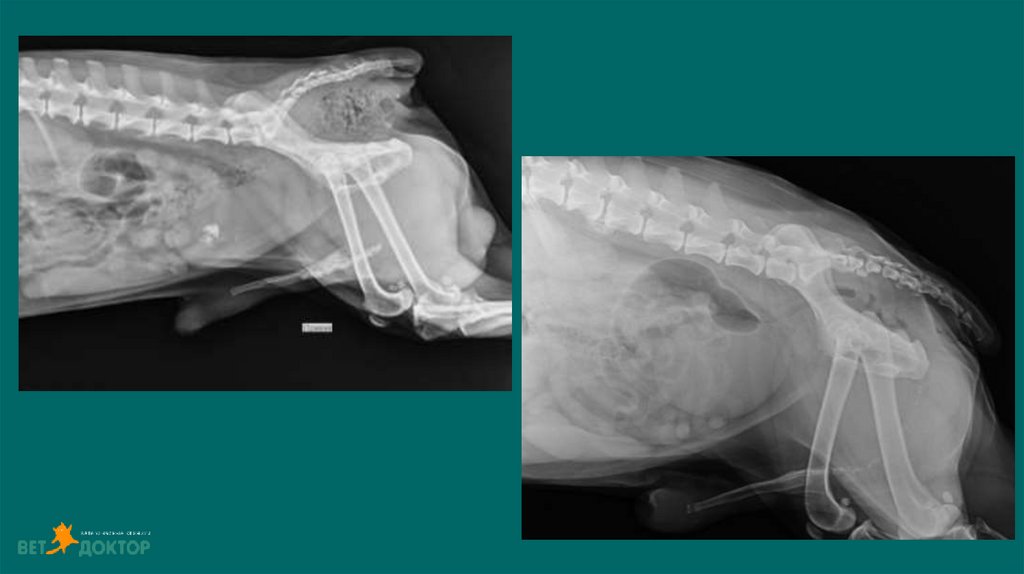

49. Тотальный гидронефроз

51. Видео

Тотальный гидронефроз

o Наличие обструкции – лоханка более 8-13 мм

o Гиперкалиемия, олигурия, анурия (связанные с полной обструкцией

мочеточников)

o

Если 48 часов отрицательная динамика по узи(размер лоханки) и не

разрешается азотемия на консервативном лечении.